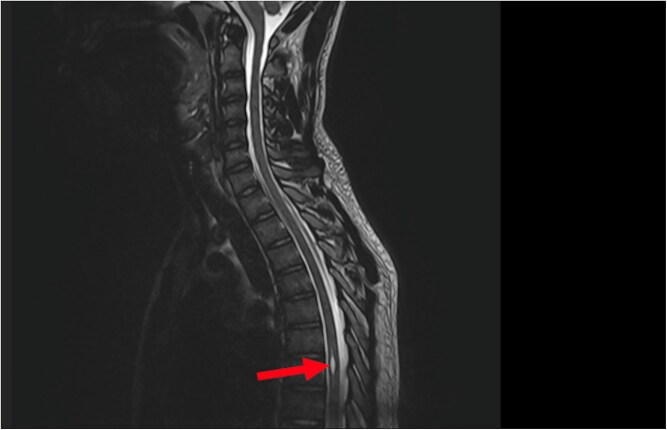

Introduction: Syringomyelia is a rare pathology which is rarely revealed by urinary urgency. We report the case of a 20-year-old man with persistent urinary urgency and pollakiuria for two years, with no identifiable organic cause despite a thorough urological work-up. A transient episode of lower limb atony prompted spinal MRI, which revealed an isolated syrinx at the T6-T7 level, without associated Chiari malformation or conus medullaris involvement. The final diagnosis was vesico-sphincter dyssynergia with overactive bladder syndrome secondary to idiopathic thoracic syringomyelia. Conservative management, including anticholinergic therapy and psychological support, led to significant clinical improvement.

Conclusion: As illustrated by our case, syringomyelia may present exclusively with urinary symptoms. However, such presentation is uncommon. This case highlights the importance of considering spinal cord pathology in the differential diagnosis of unexplained urinary symptoms, even in the absence of overt neurological deficits.